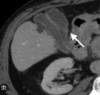

7

Q

A

Hígado graso